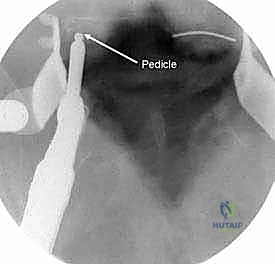

السويقات الفقارية (Pedicles): دعامة التثبيت الأساسية والمحورية

تعتبر السويقة الفقارية (Pedicle) جسرًا عظميًا أسطوانيًا يربط الأجزاء الخلفية للفقرة (القوس الفقري) بالجسم الفقري الأمامي الضخم. في جراحة دمج الفقرات الحديثة، تعتبر السويقة نقطة التثبيت الرئيسية والأقوى للمسامير المستخدمة في العملية (Pedicle Screws). يختلف شكل وحجم وزاوية السويقات بشكل كبير على طول العمود الفقري، وفهم هذه الفروق الدقيقة أمر بالغ الأهمية للجراح لضمان وضع المسامير بأمان تام وفعالية قصوى دون الإضرار بالأعصاب أو الأوعية الدموية.